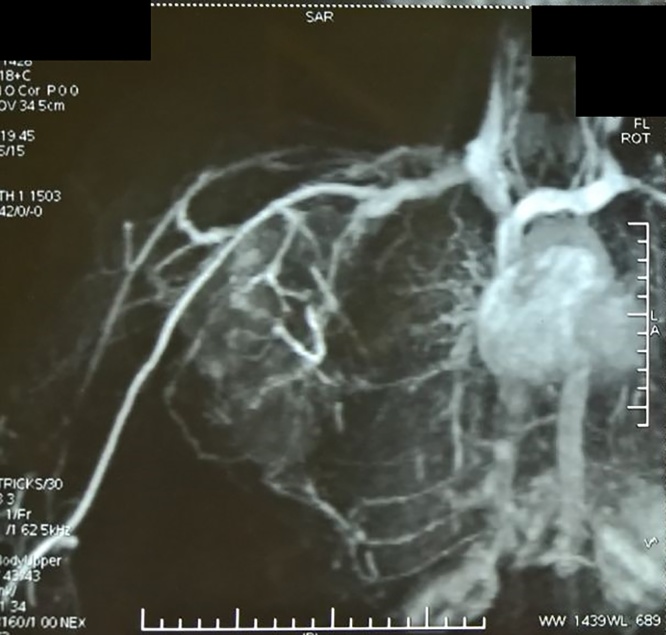

Magnetic Resonance Angiogram showed feeders from the branches of right subclavian and axillary arteries and venous drainage into the right subclavian vein (Fig. 6).

Fig. 6.

Magnetic Resonance Angiogram showing feeders.

Owing to the size, location and findings of the Magnetic Resonance Angiogram we initially suspected a Soft Tissue Sarcoma, but to our surprise, on further investigation the mass was revealed to be Nodular Fasciitis.